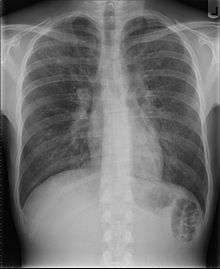

| End-stage pulmonary fibrosis of unknown origin, taken from an autopsy in the 1980s. | |

Prolonged ILD may result in pulmonary fibrosis, but this is not always the case. Idiopathic pulmonary fibrosis is interstitial lung disease for which no obvious cause can be identified (idiopathic), and is associated with typical radiographic (basal and pleural based fibrosis with honeycombing) and pathologic (temporally and spatially heterogeneous fibrosis, histopathologic honeycombing and fibroblastic foci) findings.